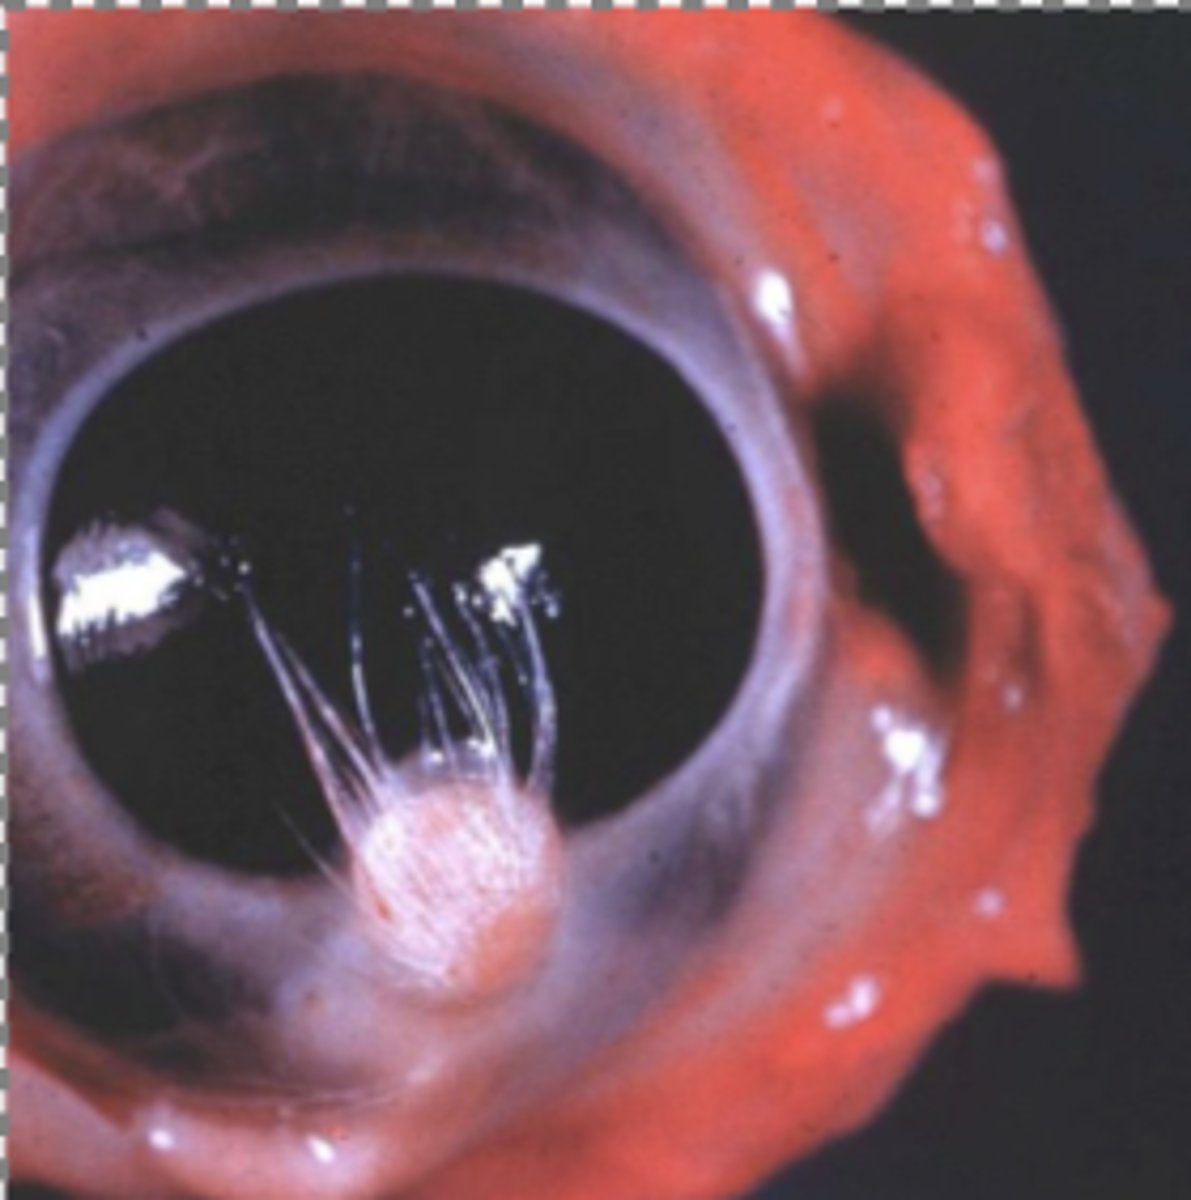

Heart: severe chronic active necrosuppurative endocarditis

Describe this lesion in a horse.